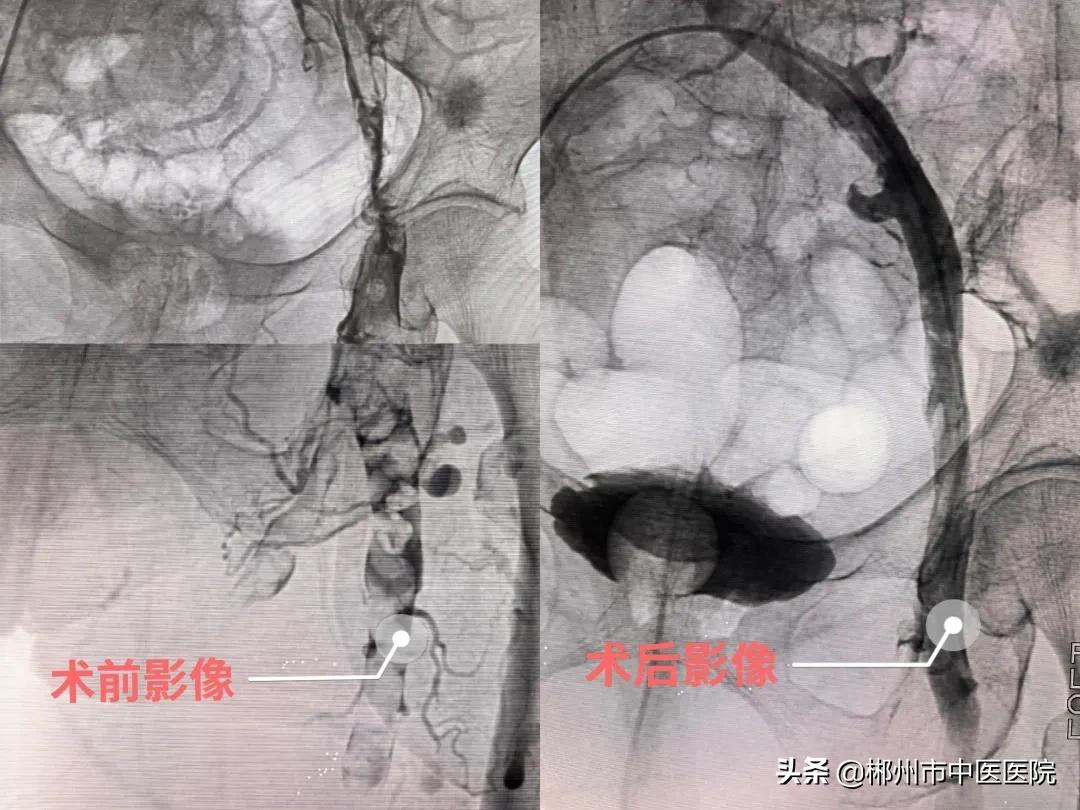

我院介入科主任李孝生博士团队综合考虑后决定为曹奶奶实施更为安全有效的办法——经皮下肢静脉血栓机械清除术,通俗一点来说也就是通过一个针眼大小的穿刺点送入一根很细很柔软的血栓抽吸导管(AngioJet导管),将血栓打碎后把血栓抽出来,血管也再次变得光滑起来,手术后曹奶奶的腿肿、腿痛很快就恢复如初,第二天就开始像正常人一样行走了。医护人员也再次看到了曹奶奶脸上灿烂的笑容,那是发自内心的喜悦和感激。

郴州市中医医院介入科在市内率先成功开展经皮机械血栓清除术。以介入科主任李孝生博士为首的介入微创诊疗团队,开拓创新,勇攀高峰,多次成功救治各类血栓患者,技术已十分娴熟。